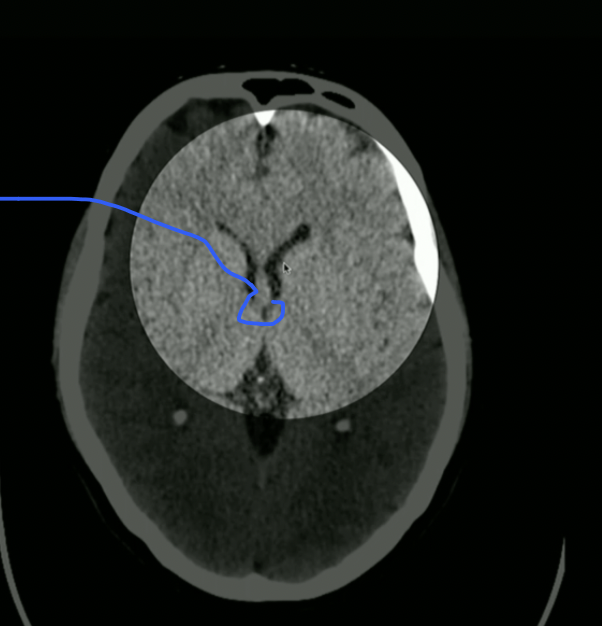

<p>What is highlighted?</p>

What is highlighted?

• 3rd Ventricle

• CSF then goes to Cerebral Aqueduct